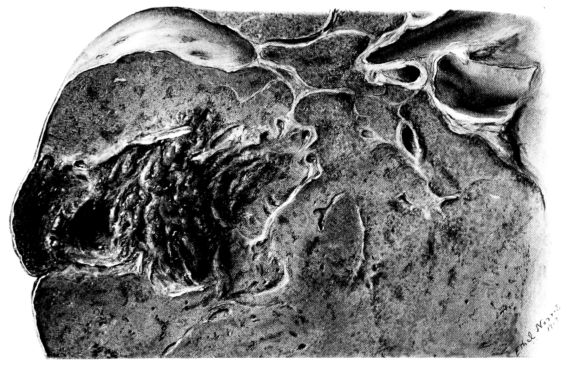

FIG. I. AUTOPSY NO. 99. ACUTE HEMORRHAGIC AND ULCERATIVE LARYNGOTRACHEITIS.

Early in the disease the congestion and the hemorrhages that have been described in the mucous membrane of the nasopharynx (14 and 94) are also conspicuous features in the lining of the trachea and bronchi (Fig. I). This membrane is swollen, turgid, red, and covered by a copious, mucous exudate which may be clear, but much more frequently is blood-stained or opaque and yellowish in color. The blood, variable in amount, may be fresh and red; and after the mucous exudate on the surface is removed, more intense red foci stand out on the congested base (47, 90, 157). Frequently, as the bronchi are approached, the red color of the mucosa becomes more intense and may have a garnet tinge. Membranes such as are encountered in the more usual necrotizing inflammatory processes, like diphtheria, have not occurred in the trachea and larger bronchi in this series (108, 128, 157).[3] The exudate peels off readily, and as indicated above, leaves a velvety red surface, 14dotted here and there with darker or more intensely red foci. Small ulcerations of the mucosa occur, but are inconspicuous (82, 156). As the finer ramifications of the bronchi are approached, the accumulation of the exudate in their lumina becomes more and more marked, and on cross section of the lung, they often stand out conspicuously on account of their increased size and projecting, seromucous, blood-stained content (101, 149, 162).